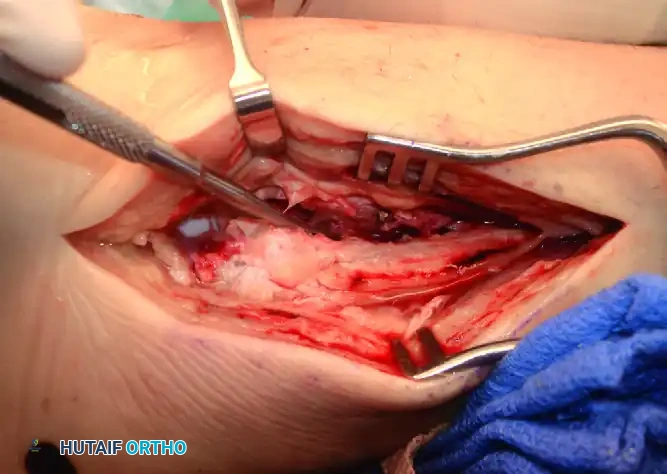

REPAIR OF ACUTE RUPTURE OF THE DELTOID LIGAMENT

Isolated partial ruptures of the deltoid ligament are common, but isolated complete ruptures are exceedingly rare. Typically, acute ruptures of the deltoid ligament are associated with a fracture of the lateral malleolus or disruption of the distal tibiofibular syndesmosis.

Harper reported on 42 patients treated surgically for ankle fractures with complete disruption of the deltoid ligament, without primary deltoid repair. The functional results were highly satisfactory, provided that the surgical reduction of the lateral malleolus was perfectly anatomical and maintained until bone healing was complete. In these cases, the medial joint space reduced spontaneously, and no late medial instability was noted.

Indications for Medial Exploration:

Surgical exploration of the medial ankle is mandatory when there is evidence of severe, irreducible displacement at the time of injury. During attempted reduction of the laterally displaced talus, soft tissue can become incarcerated in the medial clear space. The most common offending structures are:

1. The posterior tibial tendon.

2. The proximal stump of the avulsed deltoid ligament.

Surgical Pitfall: Do not confuse an irreducible mortise with an isolated rupture of the posterior tibial tendon. If the medial clear space remains widened after anatomical fixation of the fibula, you must open the medial side, extract the enfolded tissue, and repair the deltoid ligament directly.